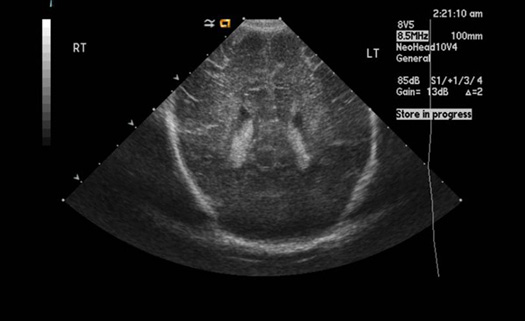

Ultrasound (US)

US does not penetrate bone easily. Hence, it's not useful with adult head.

It is useful in children where fontanels are not closed.

US of normal neonatal child is shown on left.

No radiation is involved with US and hence, ideal for use in neonatal skull.

Children have unique neurological problems like congenital abnormalities, brain tumors and hydrocephalus where US is useful.

It is a non-invasive study with no complications and can be done by the bedside.

Normal neonatal child